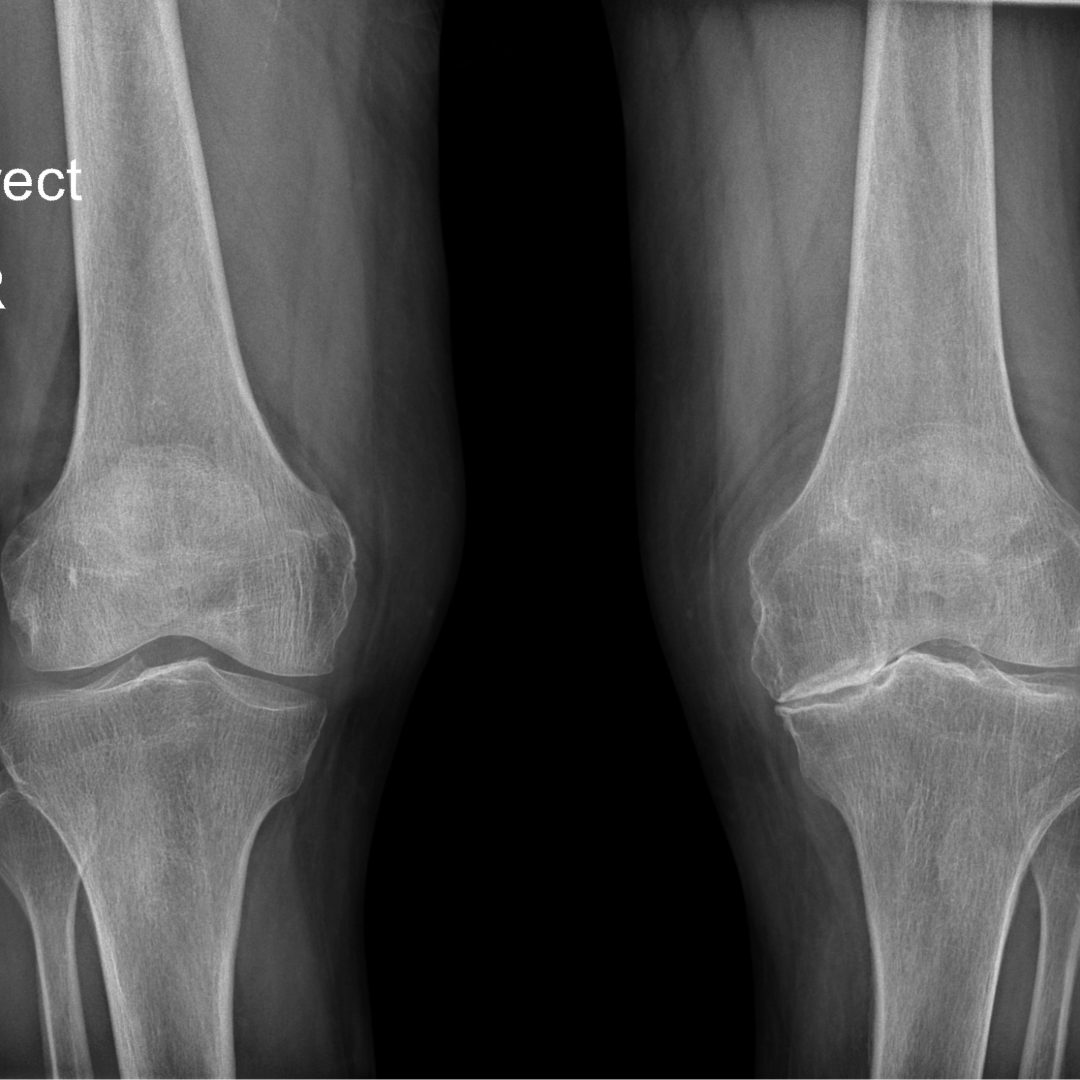

Imaging tests provide a snapshot of your body's internal structures, but they don't always tell the whole story. A physical therapist is skilled at assessing how your body moves and functions, which can reveal issues that an image alone cannot. They can determine if your condition can be treated effectively with physical therapy, even when a scan suggests something more severe or fails to show a problem at all.

Many people have "abnormal" findings on their imaging scans, like bulging discs or rotator cuff tears, without experiencing any pain. A physical therapist’s evaluation focuses on your symptoms, movement patterns, and functional limitations. This hands-on assessment provides critical context that an image simply can’t offer, ensuring your treatment targets the true source of your discomfort.